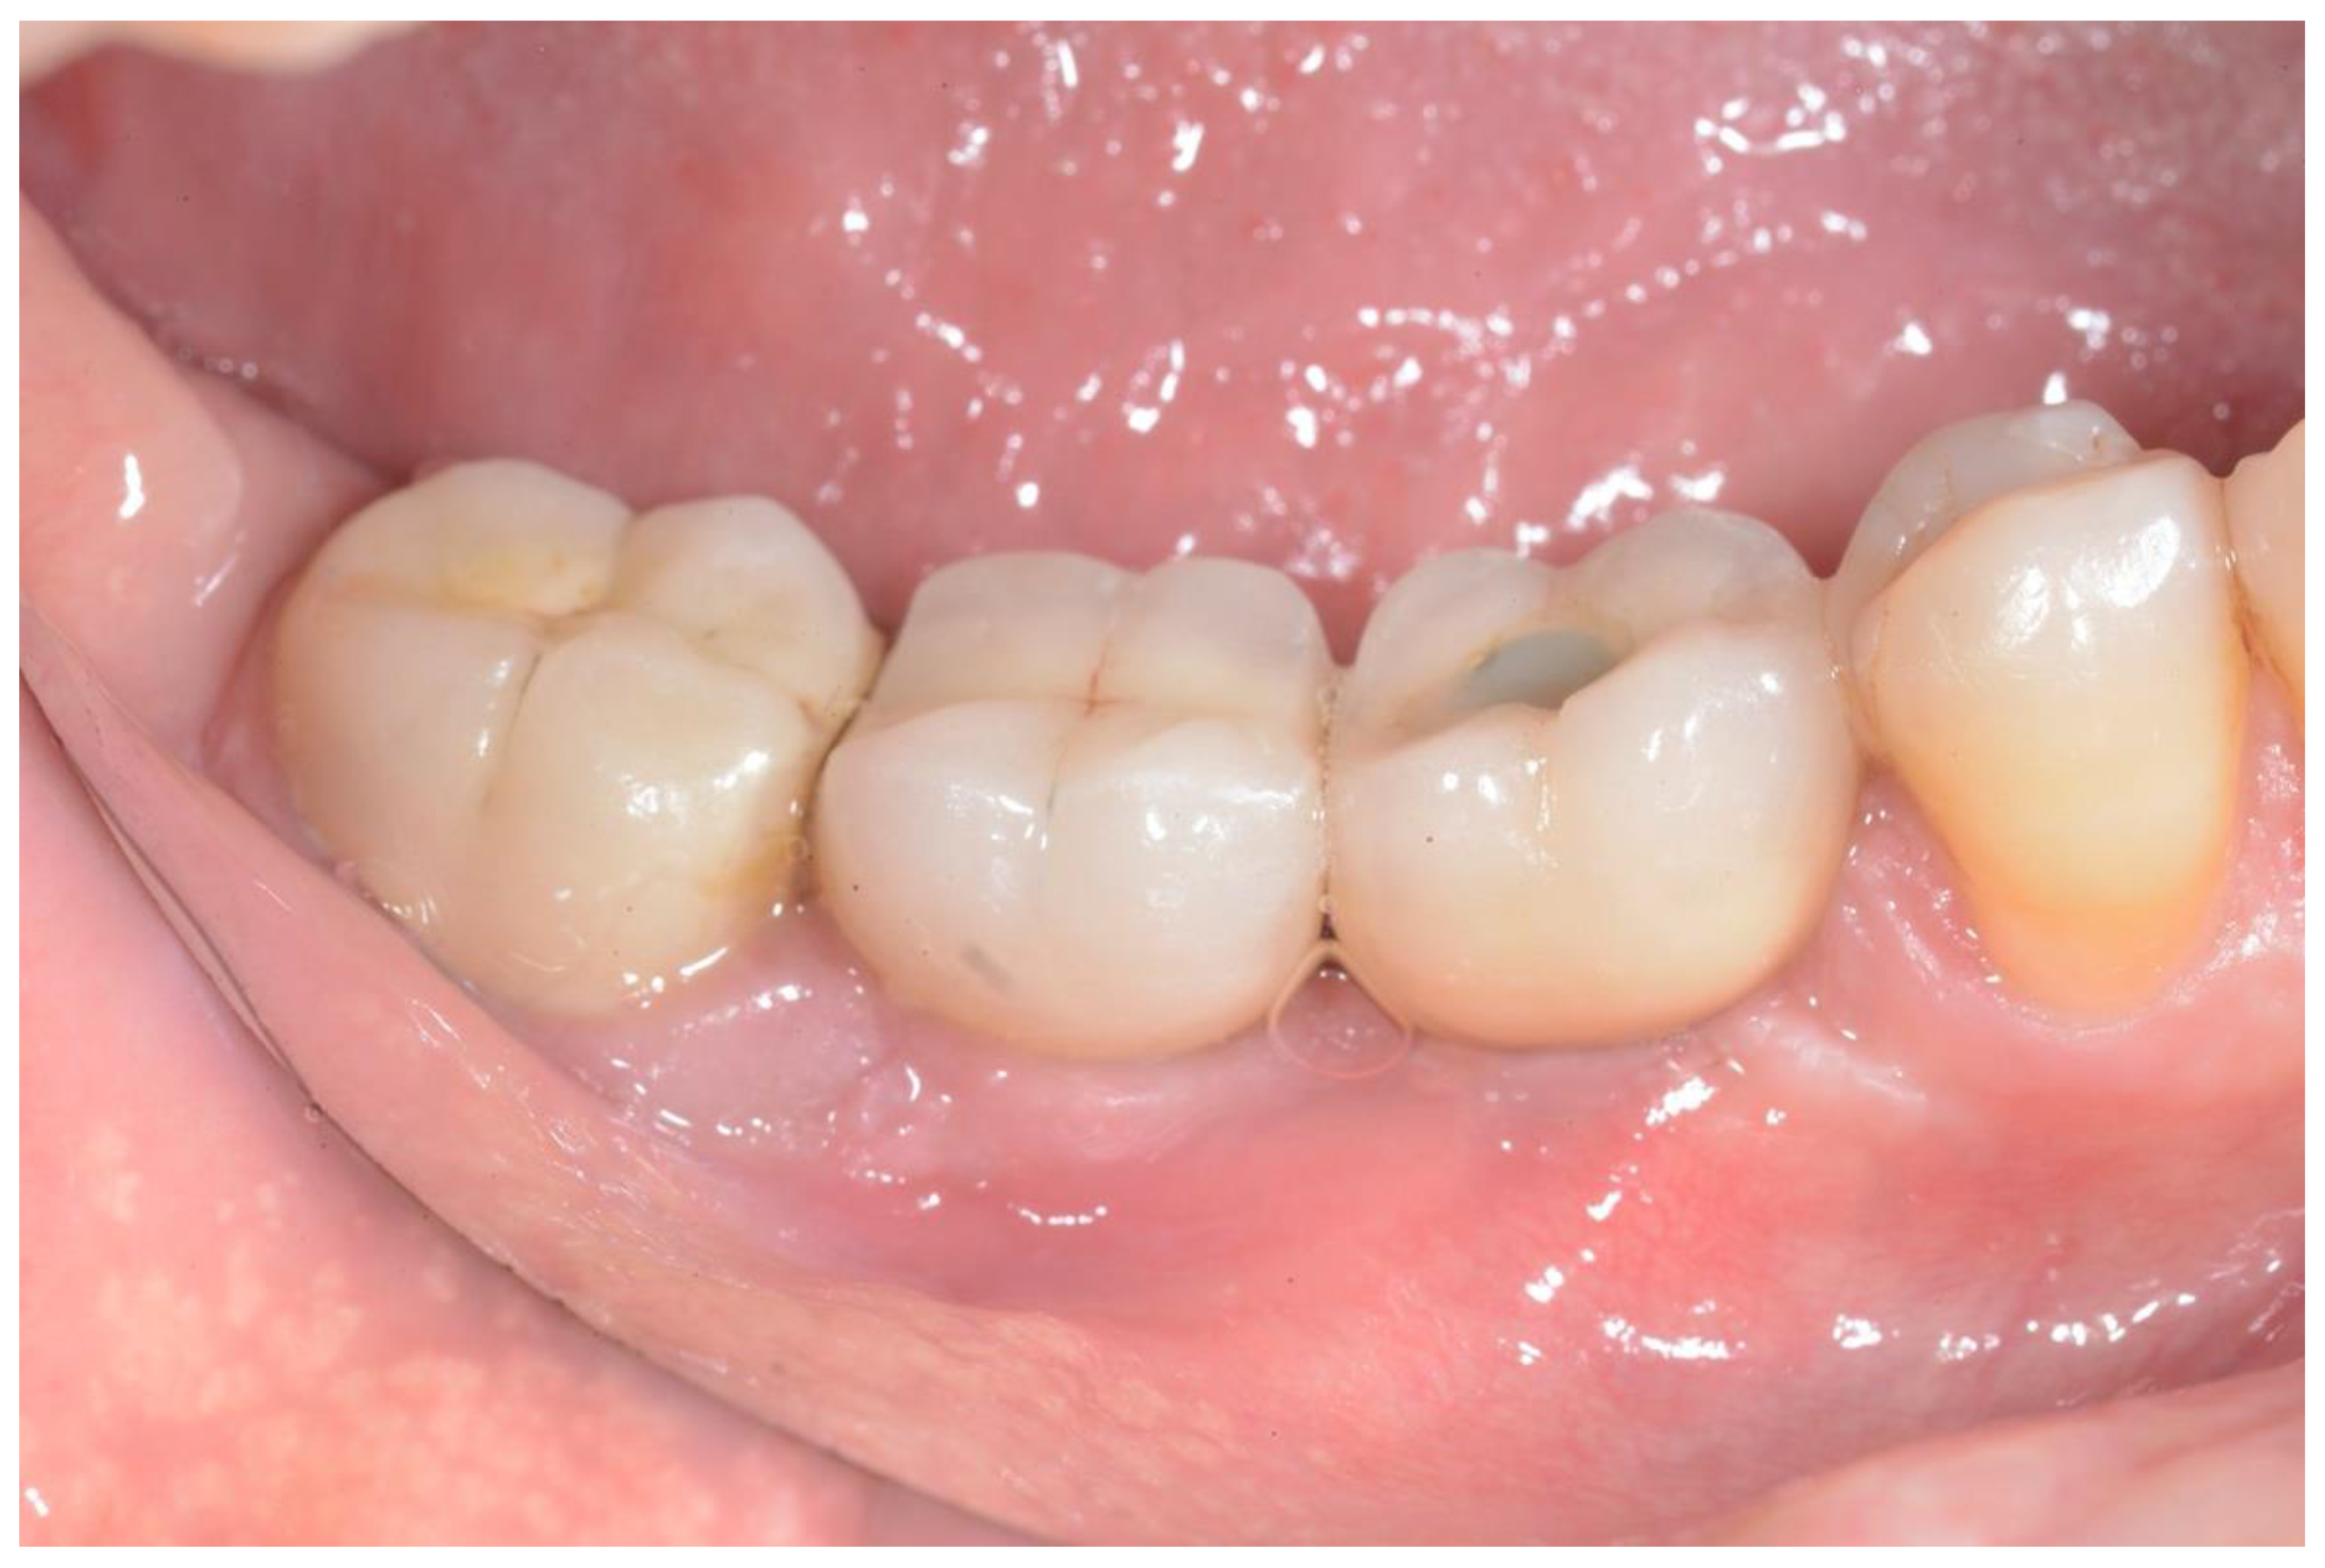

Peri-Implantitis: Application of a Protocol for the Regeneration of Deep Osseous Defects. A Retrospective Case Series

3. Results